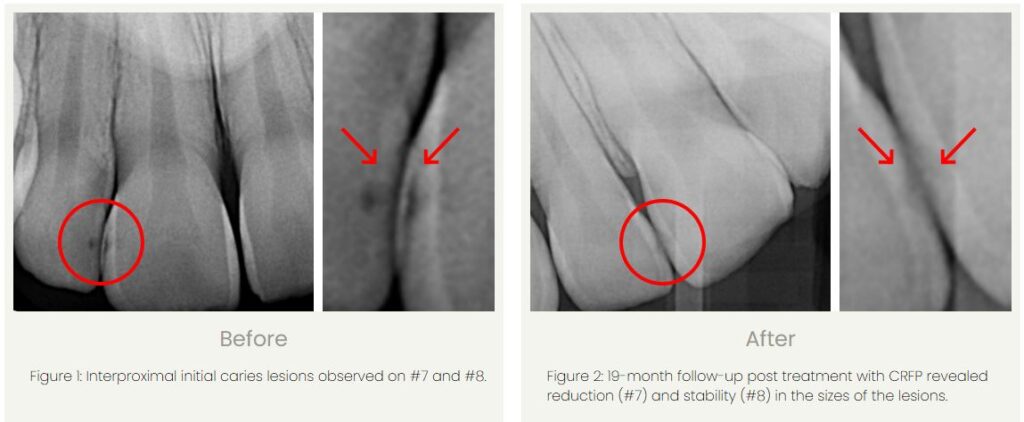

We can treat early-stage cavities before it’s too late.

Drill-free, injection-free, and pain-free enamel regeneration is now available at MOD Squad Dental.